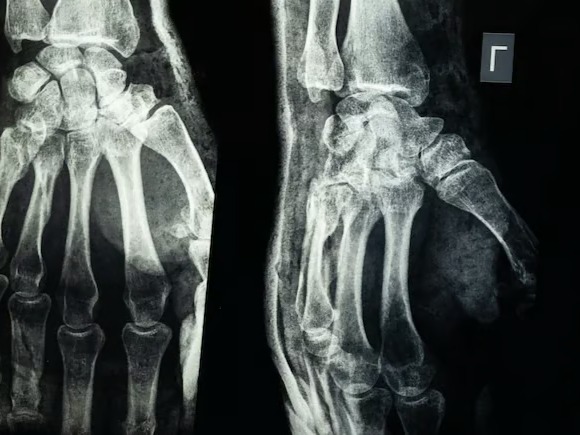

Röntgen filmi - NDTV

- Zhejiang’da geliştirilen “Bone-02” adlı yapıştırıcı, üç dakikada kemik sabitlemesi yapabiliyor.

Araştırmacıların verdiği bilgilere göre yapıştırıcı, kanlı ve zorlu ortamlarda dahi iki ila üç dakika içinde güçlü bir sabitleme sağlayabiliyor.

CCTV’nin aktardığına göre, ürün 150’den fazla hastada test edildi ve güvenlik ile etkinlik kriterlerini geçti. Yapıştırılan kemikler, 180 kilogramın üzerinde bağlanma kuvveti, 0,5 MPa kayma dayanımı ve 10 MPa basınç dayanımı gösterdi.